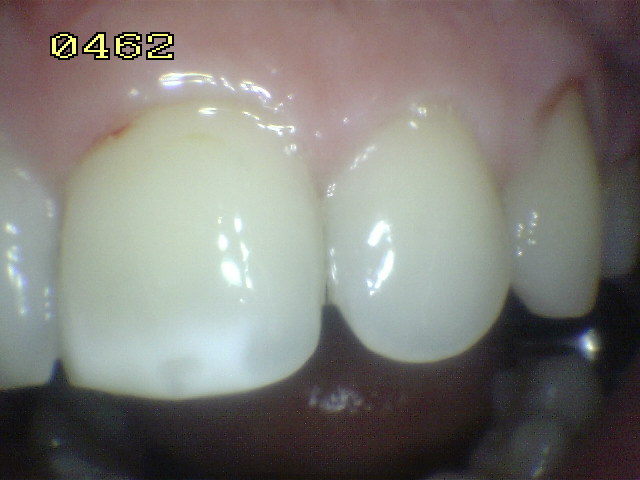

Una mancha oscura de dentina que se observa a través del esmalte intacto,  adyacente a la fosa y reborde marginal,  indica la presencia de desmineralización. (Imagen 0229)

Las Radiografías Bite-Wing son un pre-requisito cuando se considera una restauración con sellador. Éstos no deben mostrar evidencia de caries interproximal que pueden indicar que una restauración deba ser  más extensa. Debe ser considerado que el tamaño real de la lesión es normalmente más grande que la imagen radiográfica. La Transiluminación  también puede ser un beneficio para el diagnóstico de caries oclusal y caries interproximal.